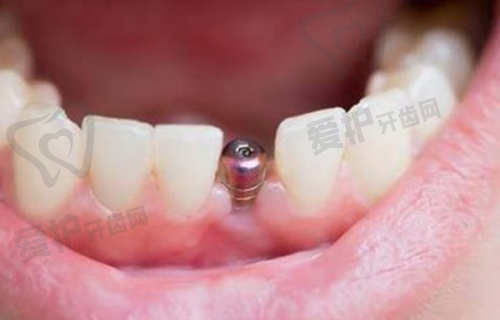

登腾种植牙是一种将人工牙根植入缺牙部位的牙槽骨内,待其与牙槽骨紧密结合后,再安装牙冠的牙齿修复方式。它具有稳固性强、美观度高、使用寿命长等优点。与传统的假牙相比,登腾种植牙不会出现松动、移位的情况,能够更好地修复咀嚼功能。而且,它的外观与真牙几乎没有差别,不会影响患者的面部美观。正是因为这些优势,登腾种植牙在口腔修复领域越来越受欢迎。

首先,患者需要到兰州诺贝尔口腔进行全方面的口腔检查,包括口腔X光片、CT扫描等,以确定牙槽骨的情况和是否适合种植。然后,简波简院长会根据检查结果制定个性化的种植方案。在种植手术中,医生会在局部麻醉下将人工牙根植入牙槽骨内。这个过程一般不会有明显的疼痛感。术后,患者需要遵循医生的嘱咐进行护理,等待人工牙根与牙槽骨结合。通常需要几个月的时间,待结合牢固后,再安装牙冠,整个种植过程就完成了。